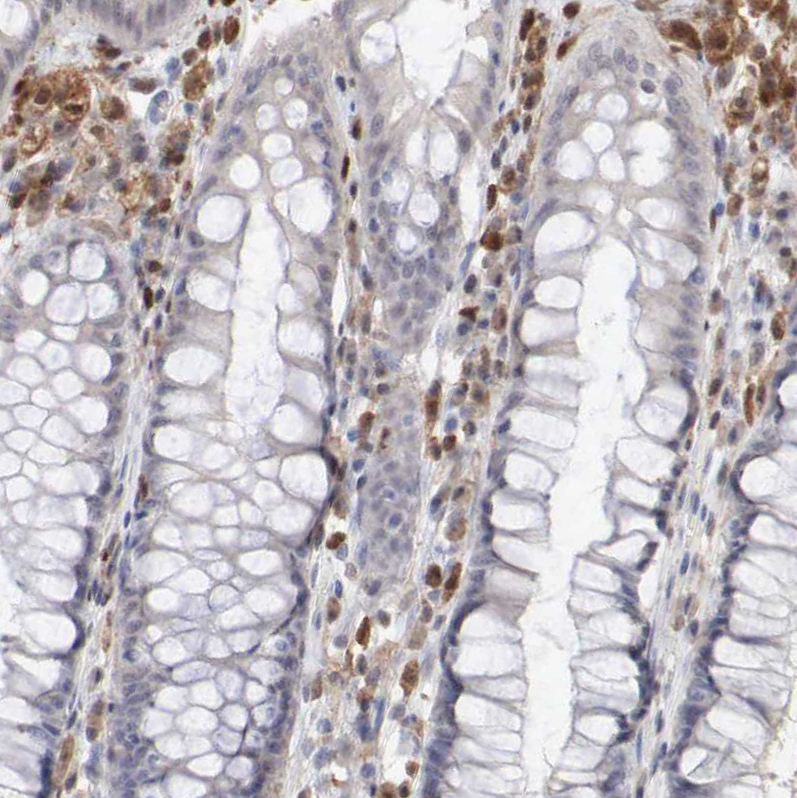

signal transducer and activator of transcription 1, 91kDa

Anti-STAT1 Antibody

Polyclonal Antibody against HUMAN STAT1